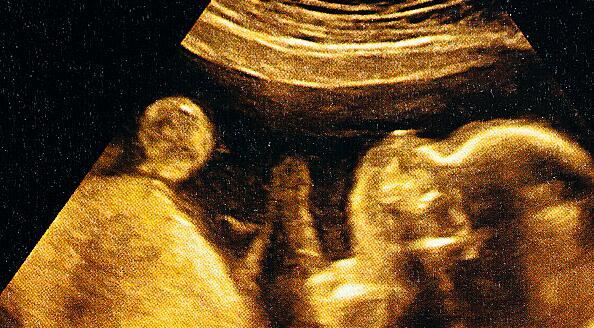

2、怀孕中期以后的胎动:

如惊跳、全身运动、孤立的上肢或下肢运动、屈伸头部、转头、转身、伸展、张口、手触脸部及打呃、打哈欠、吸吮、吞咽等。这些运动,在妊娠13—15周达最高峰,17周后逐渐减少。